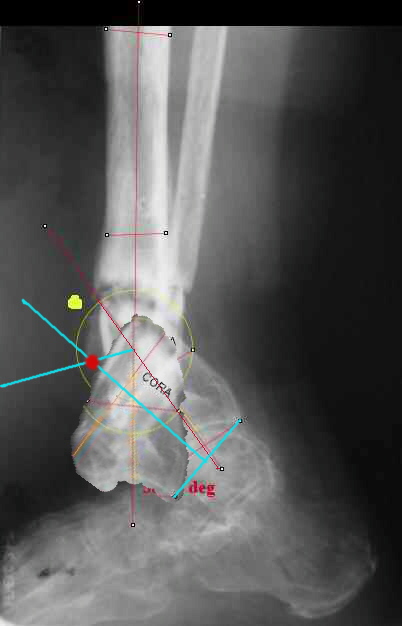

Maybe my "embedded software" is obsolete but it hints me to place hinges at the yellow point - this must result with alignment and some lengthening without translation. What do you think?

I looked at your image. I presume your yellow marker is the hinge axis? I think this should be at the CORA.